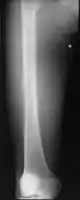

Medical imaging usually shows a well-defined wide-based bony growth on the surface of bone.[5] It can be pedunculated and irregular, giving it a "bizarre" appearance, and is not connected to underlying bone.[2]

X-ray left foot: Bizarre parosteal osteochondromatous proliferation in 2nd toe -